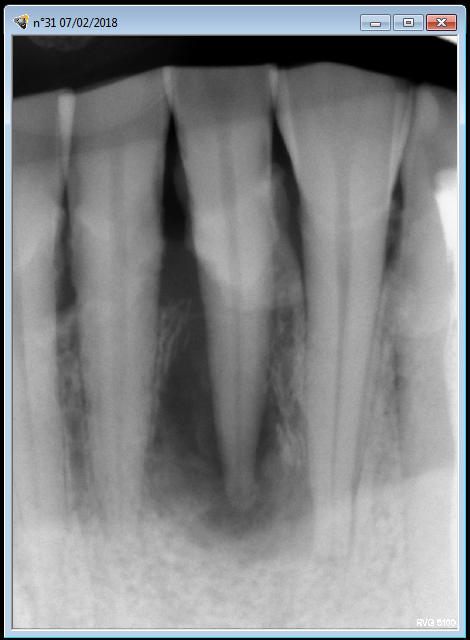

" j'ai deux dents mobiles sur deux patients différents chez qui, je pense, l'extraction-implantation pourrait se tenter... Pourriez-vous me donner votre avis ?

Autre cas, cette 31. Là, c'est peut être un peu extrême non ? Là c'est pareil ? Aucune contention ? faire une contention avec 32 41 mais sécuriserait j'avoue... Qu'en pensez-vous ?

Par contre ta 31, ç est nickel , tu fais l endo avant et hop tu racles ce qui depasse .pas besoin de mettre quoi que ce soit au bout .

31 mobile kymblw - Eugenol

ouaip ,ç est quand meme bien de supprimer la cause initiale avant toute chose , hein .

pour ta 31 il y a de fortes usures des bords libres . cela fait pense à 1 perte de calage post avec style usure des canines du bas avec un gros méplat .

ce qui veut dire que si tu ne comptes pas la raser , il faut au moins la mettre en sous occ .

mais attention ,il faut la mettre en sous occ ,y compris pendant les trajets de para-fonction .

si tu n'es pas sur de ton coup , ou si par manque de calage post , elle touche tjs ,alors oui ,il vaut mieux faire un petit calage par compo lors de la réimplantation .

lorsque tu fais l'endo tu peux faire une para apicale , mais lorsque tu feras l'extraction réimplantation ,il te faudra faire obligatoirement une anesthésie intraligamentaire ( même si tu as déjà fait une para apicale ).

l'intraligue , t'aidera à extraire sans forcer d'une part , mais surtout commencera à pré-décoller les parties molles de l'os par le jeu de la pression .

ç est un cas tranquille , ça ! t'en profiteras pour bien la detartrer aussi :-)